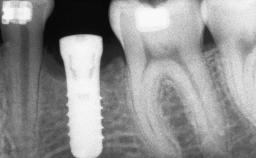

Guided Bone Regeneration (GBR) with a Particulated Autologous Graft and a ePTFE-Reinforced Membrane for Vertical Augmentation of a Single-Tooth Edentulous Space in the Esthetic Zone

# of Implants 1

Type of Implants Two-Piece

Bone Augmentation Staged|Vertical